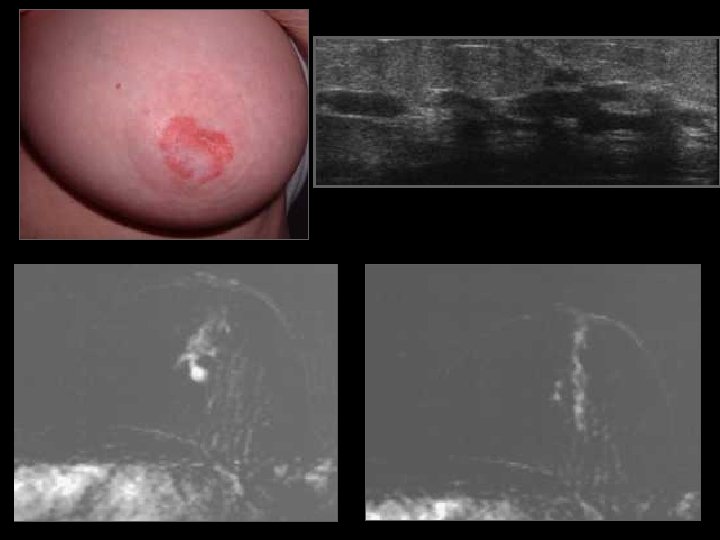

D face ext 46 ans, placard QSE droit de 4 cm palpé par la gynécologue

U Q Sup droits Biopsie : CLI

Détection d’un cancer occulte • Ganglion axillaire métastatique • Métastases osseuses, … • Maladie de Paget sans signe mammographique/ ou discordance